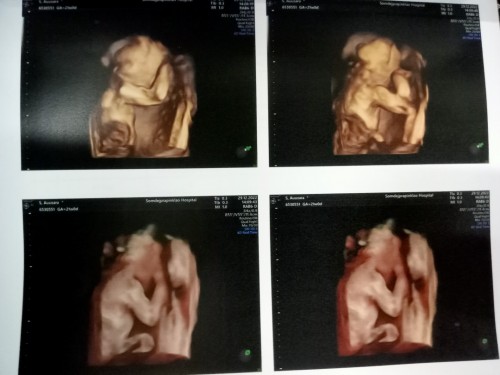

บ้านนี้ได้ลูกชายจ้า น้องขี้อายมาก ลุงหมอชาวด์เป็น ชม. ไม่ยอมหันหน้ามาให้แม่ดูเลย